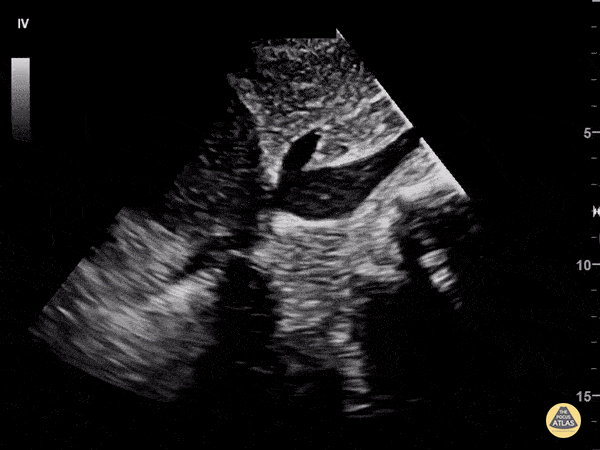

58 y/o F with PMHx of metastatic adenocarcinoma of lung presents with progressive SOB for one week. The patient was tachycardic to 103, normotensive, afebrile, mildly tachypneic and saturating 95% on room air. EKG demonstrated sinus tachycardia without electrical alternans. POCUS revealed a large, complex, loculated, anterior pericardial effusion. Sonographic findings of right atrial/ventricle collapse and IVC dilatation confirmed cardiac tamponade. In this long-axis subxiphoid view, the IVC is seen enlarged and has minimal respiratory variation. Common ultrasound findings of cardiac tamponade include: RV end-diastolic collapse, RA systolic collapse, plethoric IVC, septal “bounce”, decrease of mitral valve inflow velocity >25% with inspiration. Echocardiography is the modality of choice to evaluate for pericardial effusion and to assess for cardiovascular compromise (right chamber collapse and IVC). Accurate determination of this patient’s tamponade allowed for rapid surgical intervention. Patient underwent pericardial window with partial pericardiectomy a few hours after presenting to the ED. Dr. Pumarejo, Dr. Tran and Dr. Patel. Aventura Hospital and Medical Center Emergency Medicine.